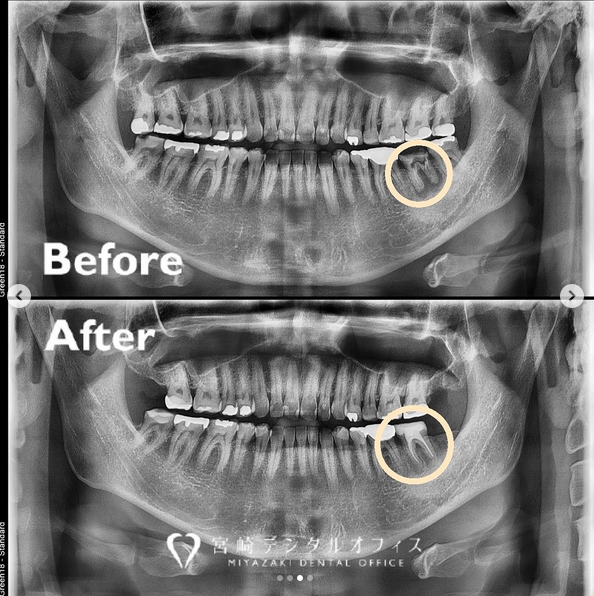

この患者様の症例は “他院では治療できないと言われた” という主訴で、たしかに左下7は精査したところ保存不可でした。

そこで、後ろにある親知らずを抜歯して、歯牙移植(自家歯牙移植=ご自身の歯を使用して移植)を行うこととなりました。

経過